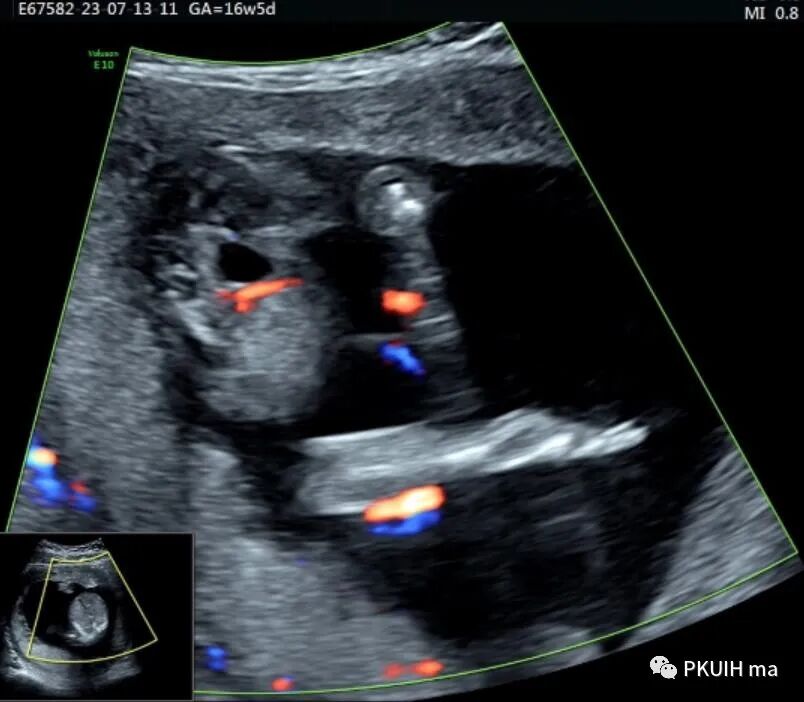

CDFI:囊肿内未见明显血流信号。

本病可于中孕及晚孕期被发现,其超声特征为肝门区囊性包块,形状呈圆形或椭圆形,位于门静脉右前方,可对门脉造成压迫。如果显示囊性包块与胆囊相通,则有助于诊断,彩超一般内部无血流信号。